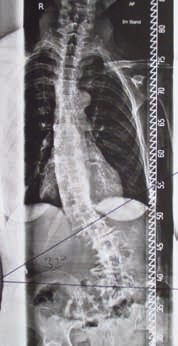

Der Autor bevorzugt individuell nach Gipsabdruck gefertigte Korrekturkorsette in Anlehnung an die Konstruktionsparameter von Chêneau/Rigo 10 11. Durch eine möglichst lotrechte Korrektur der skoliotisch verformten Wirbelsäule und der dadurch entstandenen Rumpfüberhänge soll die Orthese für den Patienten eine deutliche Schmerzreduktion erreichen. Dies wird durch gezielte Druckzonen und korrespondierende Freiräume im Sinne einer Skoliose-Korrekturorthese umgesetzt (Abb. 3a–c). Ein wichtiges Detail dieser Korsette steht bei der adulten Skoliose allerdings nicht im Vordergrund: die Derotation der Wirbelsäule durch entsprechend konstruierte Druckzonen in der Orthese. Das Korsett wird nach einem Gipsabdruck vom stehenden Patienten angefertigt. Um ein optimales Ergebnis zu erreichen, sollte man möglichst in entlasteter, aufrechter Positionierung gipsen. Hilfreich ist eine direkt vor dem Gipstermin durchgeführte Physiotherapie oder, noch besser, eine Unterstützung während des Gipsabdruckes durch einen Physiotherapeuten.